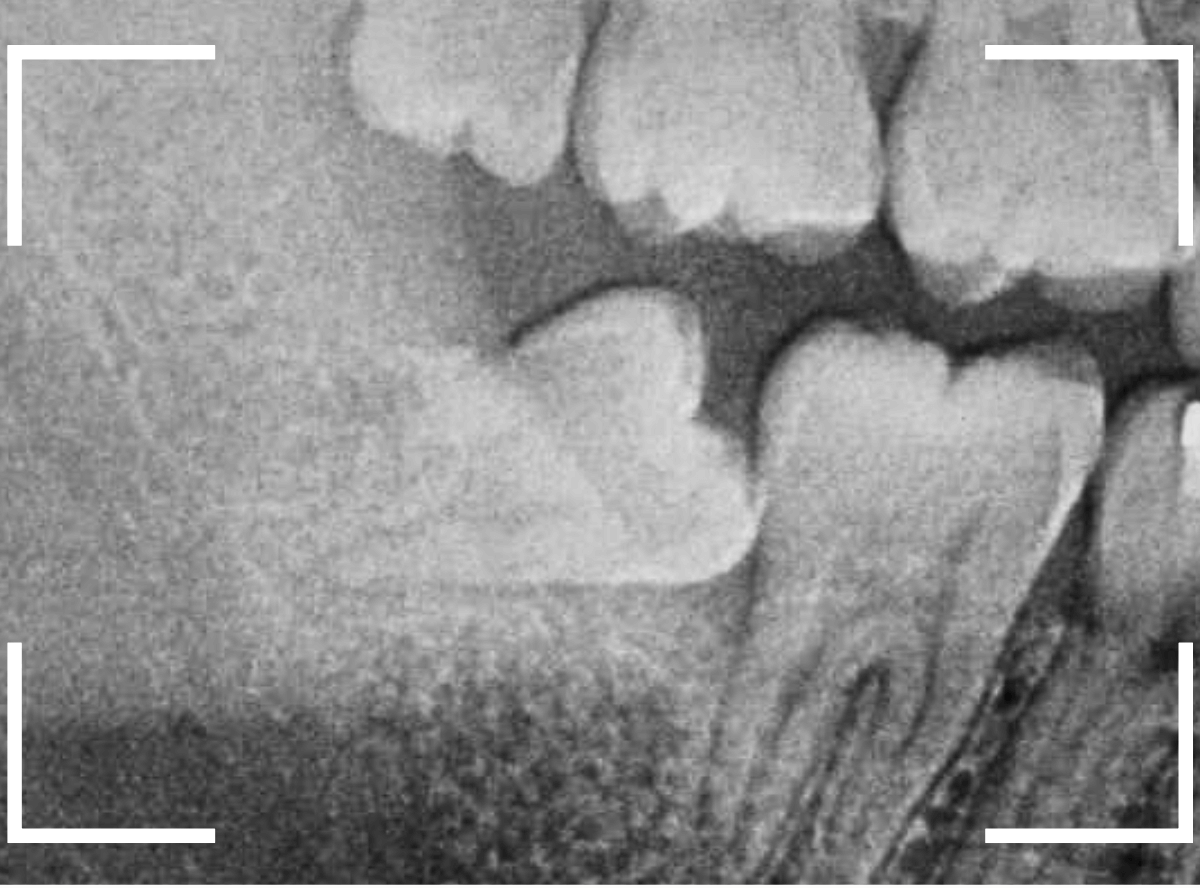

抜歯後に長期間お痛みが出たり、経過観察が必要な難しいおやしらずの抜歯ならまだしも、簡単なおやしらずの抜歯を避けてしまったがために、他の歯に悪影響を与えてしまったもったいない例も多々見てきました。

ここでは、比較的簡単なおやしらずの抜歯の例を中心にご紹介します。

このようなおやしらず、あなたはありませんか?